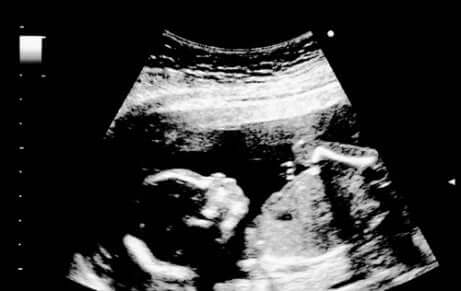

Äidin ja vatsassa kasvavan lapsen välinen side voimistuu entisestään, mikä johtuu osittain siitä, että äiti alkaa usein tässä vaiheessa raskautta tuntea sikiön liikkeet etenkin öisin. Yleensä lapsen sukupuoli selviää aikaisintaan raskauden puolessavälissä tehtävässä rakenneultrassa, mutta joissakin tapauksissa sukupuolesta voidaan saada vihiä jo 18. raskausviikolla, jos sikiö sattuu olemaan sopivassa asennossa ultraäänitutkimuksen aikana.

Sikiön liikkeet lisääntyvät ja voimistuvat koko ajan. Ultraäänitutkimuksessa sikiön voidaan nähdä venyttelevän, suoristavan ja koukistavan käsiään ja jalkojaan ja imevän sormiaan. Samassa tutkimuksessa on nähtävissä myös suun avautuminen ja sulkeutuminen, kun sikiö opettelee nielemään. 15 viikon ikäinen sikiö myös ilmeilee ja haukottelee ja toisinaan myös nikottelee, minkä äitikin voi tuntea.